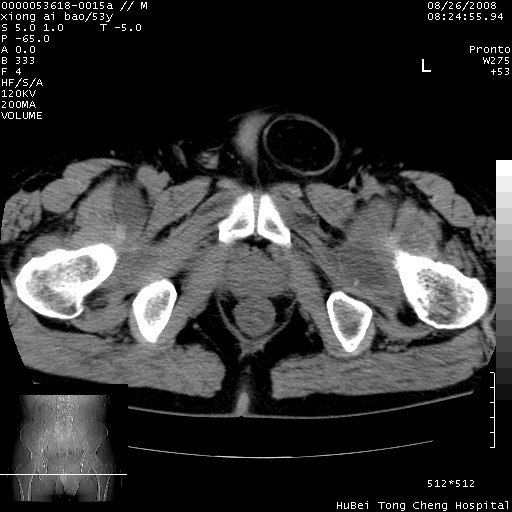

标题: CT15583:M,53Y。请老师指教分析骨盆及其他病变。 [打印本页]

标题: CT15583:M,53Y。请老师指教分析骨盆及其他病变。

股骨头坏死/腹股沟疝。

双侧股骨头无菌坏死,左侧腹股沟斜疝。

非常典型病例,双侧股骨头坏死伴双髋关节周围软组织肿胀,左腹股沟疝。

双侧股骨头坏死伴双髋关节周围软组织肿胀,左腹股沟疝。

双侧骨股头无菌性坏死,左侧腹股沟疝

双侧髋关节肿胀明显,感觉还不能排除结核。

考虑双侧髋关节结核,左侧腹股沟疝